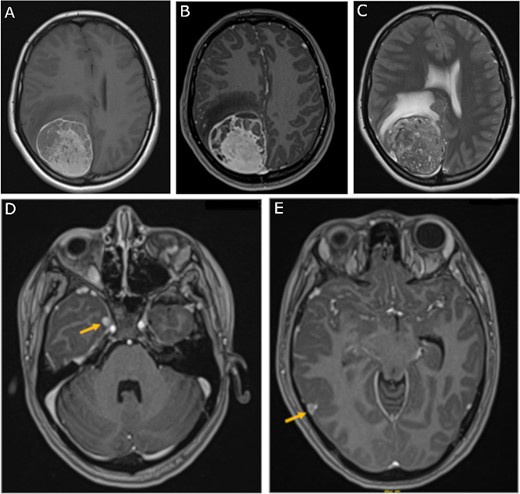

Chemotherapy and radiation therapy were not recommended due to the low-grade features on pathological examination. The patient was then discharged home at her pre-operative neurological baseline. The 3-month follow-up MRI showed no recurrence of the mass and stability of the right temporal lesions (Fig. 4).

Three-month follow-up MRI; (A) sagittal, (B) coronal, and (C) axial post-contrast T1-weighted MRI scans show peripheral contrast enhancement at the parietal resection margin with areas of nodularity related to postoperative changes without recurrence; (D, E) axial post-contrast T1-weighted MRI shows stability of the medial and lateral temporal lobe lesions.